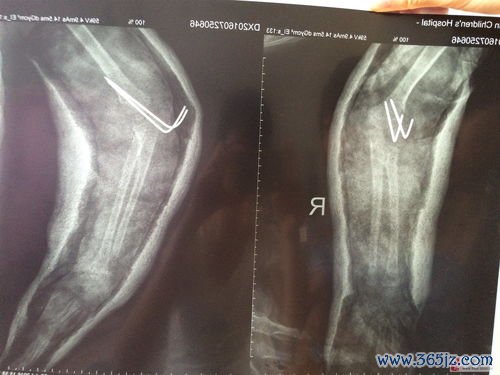

创伤:外伤

在人类纷繁复杂的生命经验中,“创伤”一词承载着多重意涵。它既指代心理上难以愈合的伤痕,也最直观地表现为身体的损伤——外伤。一道意外的伤口,一次骨折的剧痛,不仅是组织结构的破坏,更是生命与外界危险直接碰撞留下的物理印记。这类创伤超越年龄、性别与文化,是人类共有的脆弱性证明,同时也如同一面独特的镜子,映照出个体应对危机的能力、社会支持系统的效能,以及生命本身惊人...